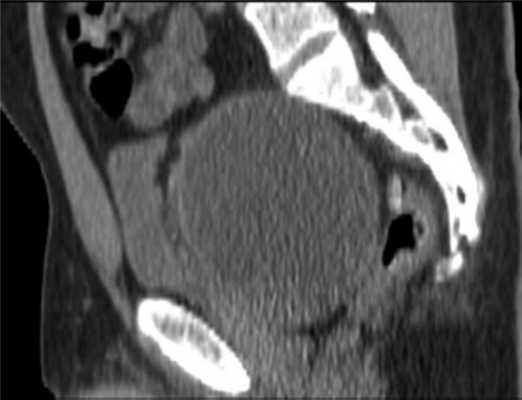

По данным магнитно-резонансной томографии (МРТ) от 10.02.2012, в полости малого таза пресакрально располагается опухоль размером 9,2×9×7 см. Верхний полюс ее на уровне тела S I позвонка, распространяется в параректальную клетчатку, тесно прилежит к прямой кишке, оттесняя ее влево (граница прослеживается). Нельзя исключить прорастание в кишку, стенки прямой кишки отечны. Опухоль прилежит к семенным пузырькам и предстательной железе (граница прослеживается); мочевой пузырь оттеснен кпереди и кверху; верхний полюс опухоли расположен между грушевидными мышцами, прилежит к передней поверхности крестца и копчика (граница прослеживается), нижний полюс опухоли расположен между волокнами мышцы, поднимающей задний проход; нижние ягодичные сосуды справа оттеснены кпереди, тесно прилежат к опухоли на протяжении 3 см (рис. 2).

Рис. 2. МР-томограммы малого таза. Пресакрально располагается опухоль размером 9,2×9×7 см. а — сагиттальный срез; б — фронтальный срез.